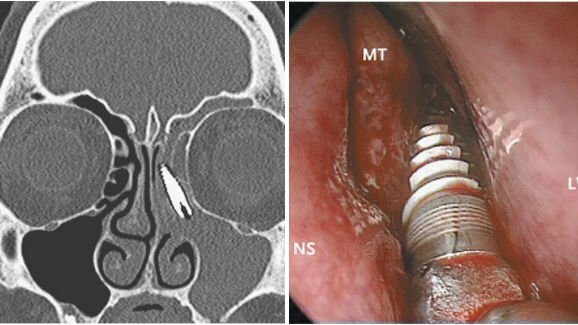

BRESCIA , Italija : Italijanski rinokirurgi so našli dislociran zobni implantat, ki je potoval navzgor skozi čeljustni sinus v etmoidne sinuse pri 57-letni pacientki, sprejeti na kliniko zaradi ponavljajočih se levostranskih sinuzitisov in obrazne bolečine levo. Zdravniki so prepričani, da se je implantat nahajal v pacientkinem sinusu vsaj eno leto.

V opisu primera avtorji z Univerze Brescia v Italiji, objavljenem 24.10.2013 v online izdaji New England Journal of Medicine, navajajo, da je pacientka imela ponavljajoča se akutna vnetja levega čeljustnega sinusa. Na CT posnetkih je bil viden tujek v levem etmoidnem sinusu.

Dve leti pred obravnavo so pacientki vsadili zobni implantat v maksilo. Ob pregledu je bil implantat v zgornji čeljusti odsoten. Rinokirurgi so ga med endoskopskim kirurški posegom našli in ga odstranili. Bolnica je bila odpuščena v domačo oskrbo naslednji dan po operaciji, prišlo je do hitrega izboljšanja simptomov.

Avtorji prispevka so sklenili, da bi lahko bil premik zobnega implantata v sinus posledica nepravilnega pozicioniranja ob vsaditvi ali pozna komplikacija periimplantitisa in resorpcije kosti.